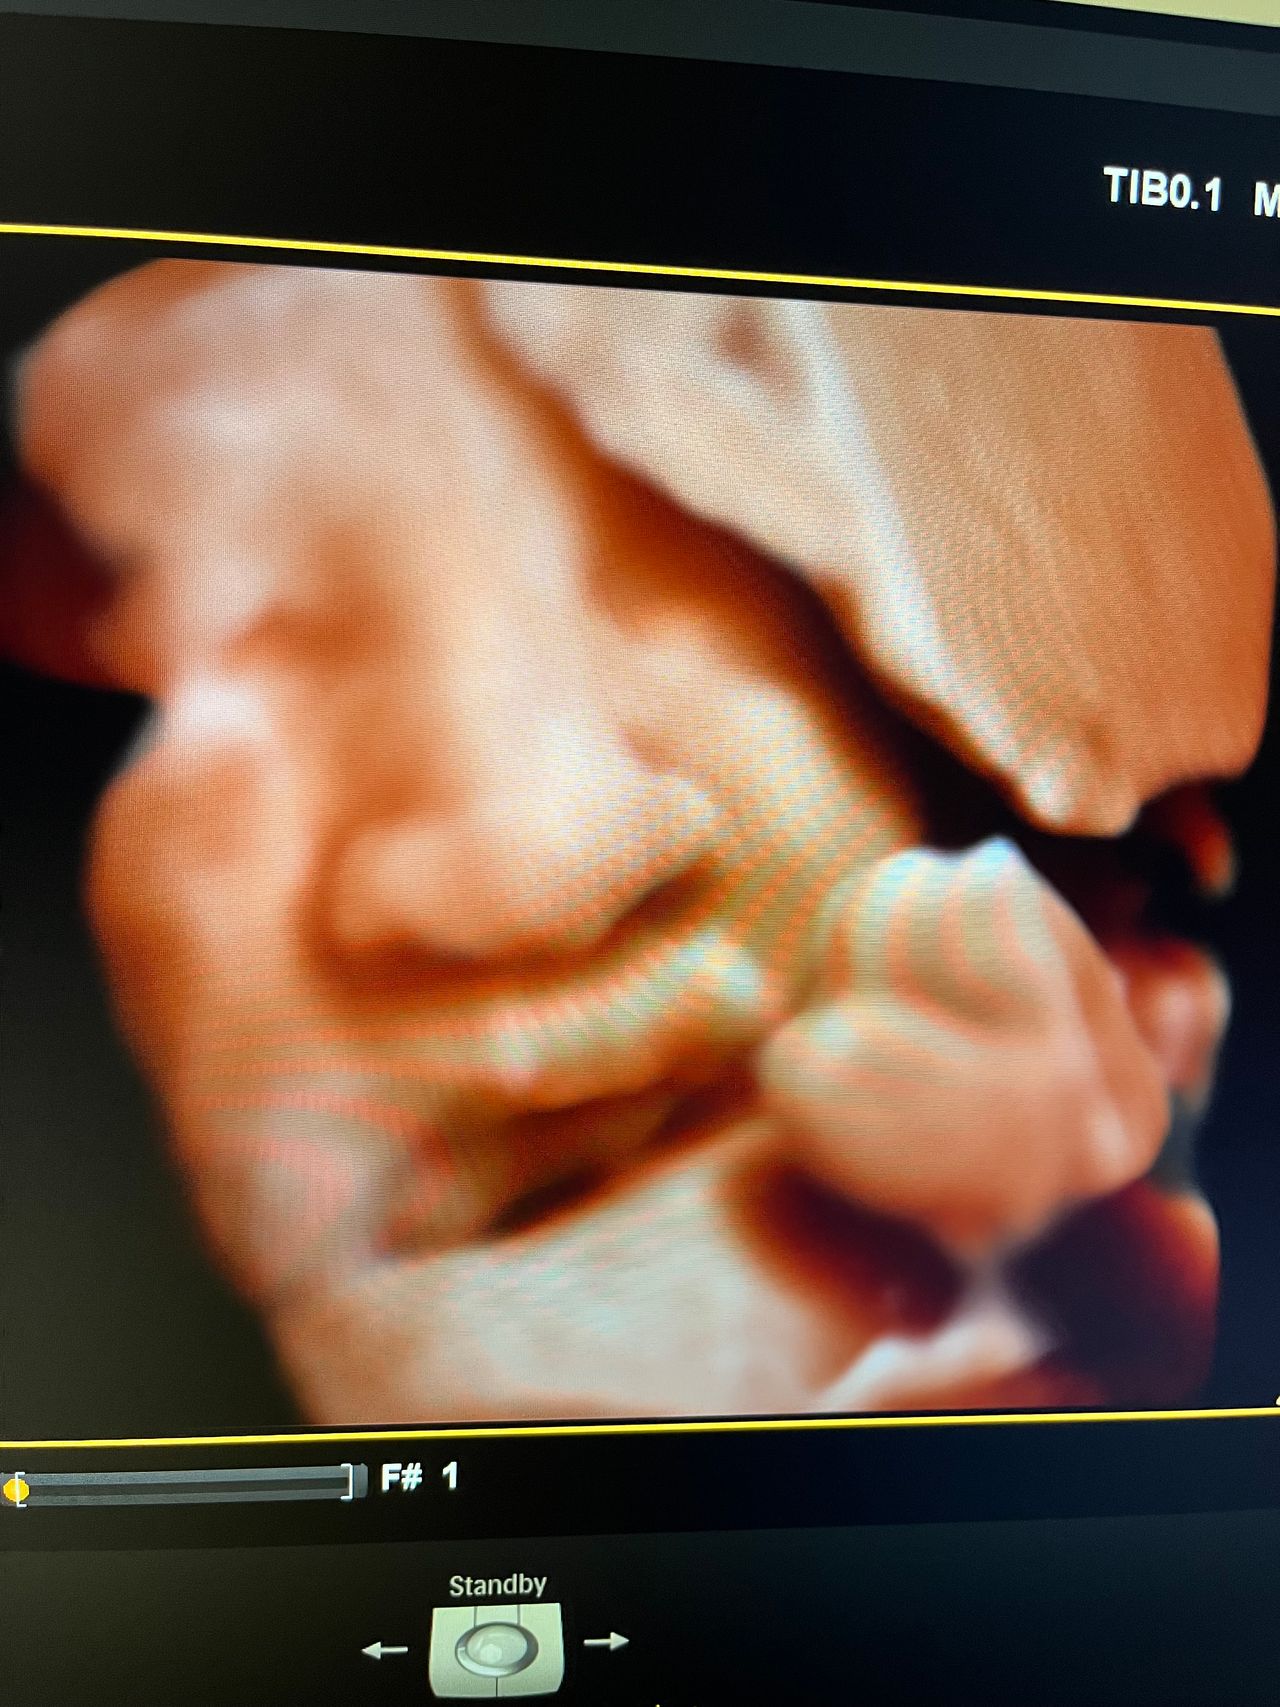

Attualmente lavoro come Dirigente medico nella SC di Ostetricia e Ginecologia dell'Ospedale Michele e Pietro Ferrero di Verduno, mi occupo prevalentemente di screening prenatale, ecografia ostetrica del I trimestre( misurazione translucenza nucale,NT), ecografia morfologica del II trimestre, ambulatorio pregresso taglio cesareo, ecografia ostetrica 3D. Seguo le gravidanze fisiologiche e quelle ad alto rischio , presto servizio in sala parto. Eseguo visite ginecologiche di I-II livello in regime ambulatoriale, counseling contraccettivo ed eventuale prescrizione pillola, inserimento spirale (IUD), dispositivo sottocutaneo (Nexplanon).

Foto e video